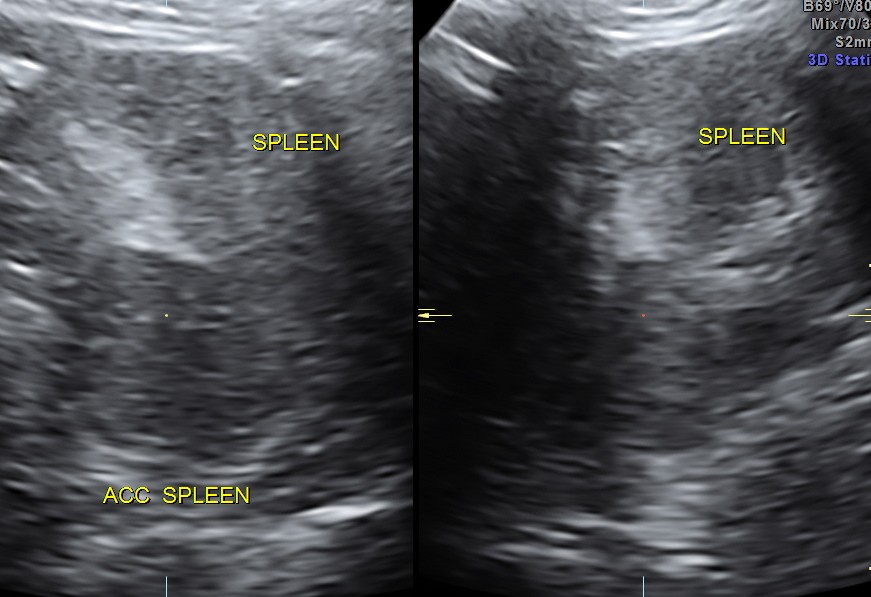

This was a 43 year old lady with chronic left loin pain.

Splenunculus was visualized,

In simpler terms this means accessory spleen.

An accessory spleen (supernumerary spleen, splenule, or splenunculus) is a small nodule of splenic tissue found apart from the main body of the spleen. Accessory spleens are found in approximately 10 percent of the population and are typically around 1 centimeter in diameter. They form either by the result of developmental anomalies or trauma. They are medically significant in that they may result in interpretation errors in diagnostic imaging or continued symptoms after therapeutic splenectomy.